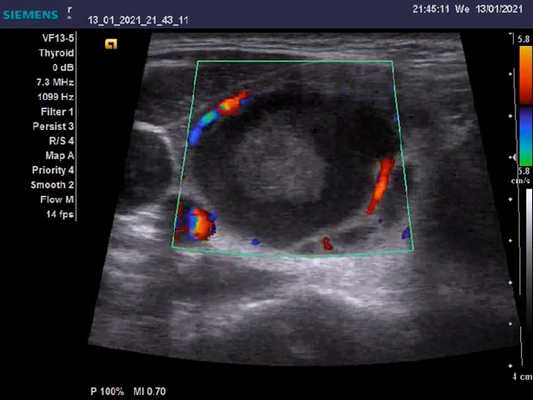

Используется линейный или конвексный датчик, по крайней мере, частотой 5 МГц или, что лучше, 7,5-10 МГц. Если доступен датчик для брюшной полости только с частотой 3 МГц, то применяется гелевый или водяной мешок, помещенный между датчиком и кожей, который позволяет грубо осмотреть шею. Технология допплеровских режимов полезна, особенно для исследования щитовидной железы (дифференциация токсических аденом, диагностика аутоиммунных заболеваний и некоторых видов рака щитовидной железы) и для дифференциации увеличенных лимфатических узлов.

Начальное ультразвуковое сканирование (скаринование в B-режиме) должно быть осуществлено в поперечной плоскости, по сильным эхосигналам воздуха в трахее отмечая срединную линию, а крупные сосуды с обеих сторон используются как «ориентиры». После поперечного УЗИ шеи, дальнейшие исследования должны сопровождаться продольными сканированиями. Впоследствии, если имеется необходимость, может потребоваться исследование с цветным допплером всей щитовидной железы (болезнь Грейвса) или образований и увеличенных лимфатических узлов и опухолей, всегда после использования метода B-сканирования.

Интенсивное кровообращение может быть продемонстрировано с помощью цветных и энергетических доплеровских методов. Пиковая скорость потока в щитовидной артерии составляет менее 25 см / с.

Цветовые и энергетйические допплеровские исследования демонстрируют поразительную гиперваскулярность. Поток в питающих артериях быстрый, более 100 см/с; снижение до менее 40 см/с при лечении интерпретируется как признак хорошего прогноза. Очаговые поражения (узлы) в щитовидной железе с плохим эхо-сигналом при болезни Грейвса-Базеда не зависят от основного заболевания и должны рассматриваться отдельно.

Типичная вегетативная аденома слабо эхогенна. Техники допплеровского картирования демонстрирует гиперваскулярность (по сравнению с окружающей тканью) в узле и гало, состоящее из сосудов. Горячие или токсичные узлы могут демонстрировать более эхогенную картину у 30% людей, а гиперваскулярность может отсутствовать в регрессивных узлах. В настоящее время нет надежных сонографических признаков, указывающих на горячий или токсический характер узлов. Таким образом, для диффузного тиреотоксикоза не существует конкретного ультразвукового шаблона. Диагноз токсического узла может быть принят только в том случае, если исключены другие (например, болезнь Грейвса, токсическая аденома). Стоит обратить внимание, что высокодифференцированные карциномы щитовидной железы также гиперсосудистые, но без ореола.

В зависимости от структуры фолликула, аденомы в основном гипоэхогенные (микрофолликулярные) или более эхогенные и довольно однородные. Их контур ровный. Низкая эхогенность при серошкальном сканировании с сосудами вокруг узла характерно для доброкачественной аденомы и поэтому лучше всего демонстрируется с помощью цветного допплера. Горячие аденомы часто проявляют гиперваскулярность.